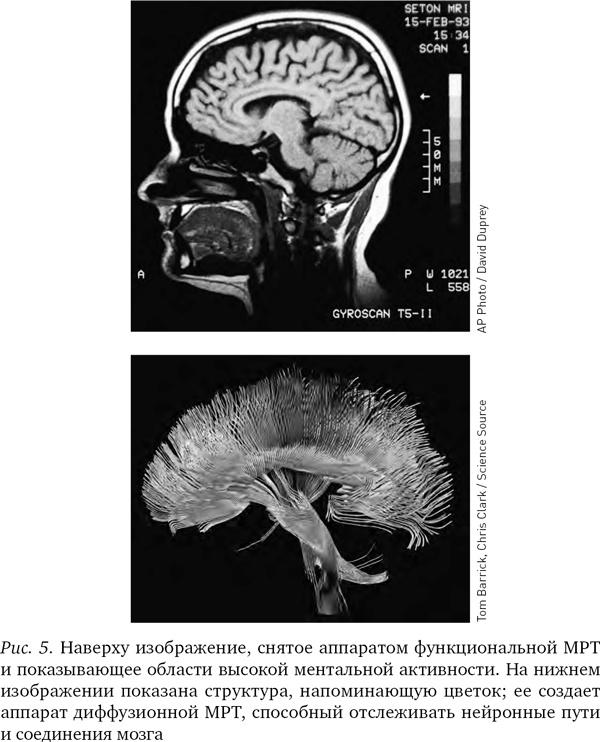

МРТ-изображения опровергли представление о том, что мышление сосредоточено в едином центре. Напротив, можно видеть, что в процессе мышления электрическая энергия циркулирует по различным частям мозга. Отслеживая путь, который проходят мысли в голове человека, МРТ-аппараты помогли пролить свет на природу болезней Альцгеймера и Паркинсона, шизофрении и других психических заболеваний.

Серьезным преимуществом МРТ-аппаратов является то, что они могут с высокой точностью выделять крохотные, вплоть до десятых долей миллиметра, участки мозга и рассматривать их отдельно. МРТ-изображение — не просто точки на двумерном экране (пикселы), а точки в трехмерном пространстве (вокселы): в результате исследования мы получаем яркое трехмерное изображение мозга, сложенное из десятков тысяч цветных точек.

Различные химические элементы реагируют на разные частоты радиоволн по-разному, поэтому мы можем, изменяя частоту волны, определять, где какие элементы находятся. Как уже отмечалось, при фМРТ в основном отслеживаются атомы кислорода в крови и измеряют кровоток, но вообще-то аппарат МРТ можно настроить на любое вещество. В последнее десятилетие появилась новая разновидность МРТ — диффузионно-тензорная; она отслеживает движение воды в объеме мозга. Вода в мозге следует по нейронным путям, поэтому диффузионно-тензорная томография позволяет получить красивые картинки, напоминающие переплетение растущих в саду лиан. Теперь ученые могут мгновенно определить, как части мозга связаны между собой.